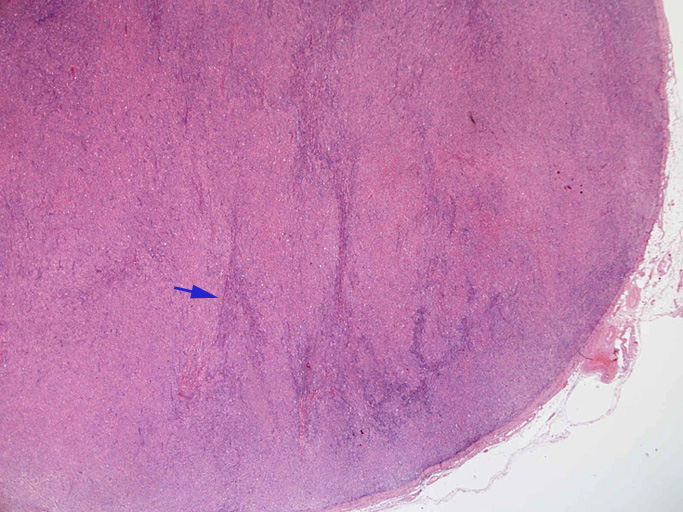

直径17mmの腫大したリンパ節。被膜は軽度線維性肥厚を示す。リンパ節の基本構造は失われ不明瞭な結節様構造が集蔟しているように見える。

- 壊死;病変内に広範な壊死巣を伴う症例が多い。採取病変がほとんど壊死に陥っていることもある

組織学的特徴より次の2群に分類される。

2.polymorphic lymphoproliferative disorder subtype(PLPD)

大型腫瘍細胞のシート状増殖はみられない。多彩な反応性背景をもちRS細胞様巨細胞が散在性に出現しホジキン病や反応性病変との鑑別が問題となる。